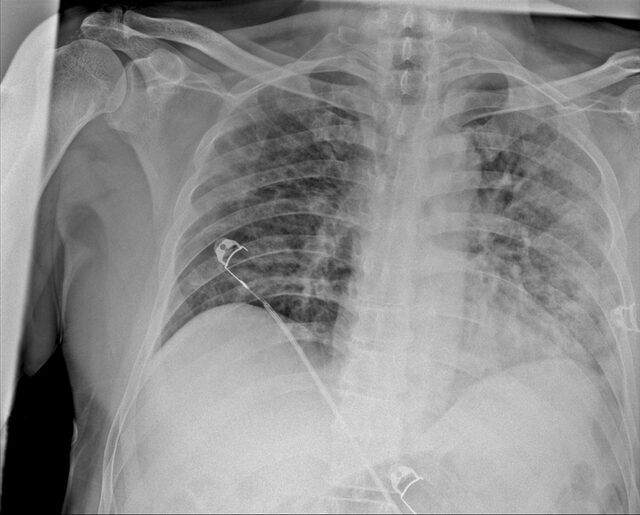

Prof. Dr. Karalezli, koronavirüs tedavisi gören hastalara ait akciğer görüntülerinden hastalığın yol açtığı tahribatı ve hastalar üzerindeki etkileri anlattı.

Tedavisine rağmen nefes darlığı şikayetleri devam eden bir hastaya uygulanan akciğer görüntülemesinde hastanın her iki akciğerinin büyük bir bölümünü enfeksiyon kapladığını tespit ettiklerini ifade eden Karalezli, "Bu hastalığın sonunun ne olduğunu bilmiyoruz. Akciğer tutulumları, bu şekilde olduğu zaman hastaları oksijen tedavisi ile gönderiyoruz. Çok yeni bir hastalık olduğu için bu seyir nasıl olacak? Geriye dönüş var mı? Takiplerle öğrenebileceğimiz bir durum." dedi.

Normal akciğer görüntüleri ile koronavirüs hastalarının akciğer görüntüleri arasında ciddi farklar bulunduğunu belirten Karalezli, şu bilgileri verdi:

"İnsanların aradaki farkları anlamaları için her iki akciğer görüntülerine de yer verdim. Görüntülerdeki beyazlıklar akciğerdeki tutulumu gösteren görüntüler ne yazık ki. Bu hastalar yoğun bakım hastaları. Filmler birbirine az çok benzeyen şekilde. Altta yatan hastalığı olanlarda ise daha kötü seyrediyor."